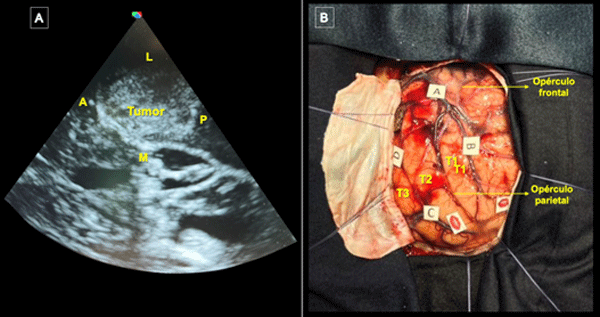

La incisión se centró en el punto temporal posterior (Figura 3), realizándose una herradura frontotemporooccipital izquierda y una cuidadosa hemostasia del colgajo. Craneotomía frontotemporal izquierda. La duramadre fue infiltrada con lidocaína al 1%. Posterior a ello se efectuó una durotomía arciforme con pedículo hacia basal exponiendo el giro temporal superior y medio. Con la paciente despierta se hizo ecografía intraoperatoria para delimitación de los márgenes tumorales, los cuales se identificaron con “tags” (Figura 4).

Figura 4. Ecografía intraoperatoria y mapeo cortical. A) Utilización de guía ecográfica intraoperatoria para identificar tumor y delimitar sus márgenes (A: Anterior; L: Lateral; M: Medial, P: Posterior). B) Marcación de los límites del tumor con tags de letras (A: Anterior; B: Medial; C: Posterior; D: Inferior) y de las áreas de mapeo positivo con presentación de anomia con dos tags de boca en región posterior de T2. Se expusieron también los giros temporales superior (T1), medio (T2) e inferior (T3) y se optó por corticotomía trans-T2.

Con la paciente despierta, se realizó estimulación cortical utilizando multitarea con flexión y extensión de miembro superior derecho combinando prueba de secuencias automáticas, test de nominación (Boston) y asociación semántica (PPTT). Para ello, se utilizó estimulación bipolar con pulso de onda cuadrada bifásica, de 1 ms de duración y frecuencia de 60 Hz. Se identificó el umbral de estimulación en 3.0 mA tras inducirse anomia en la región posterior de la circunvolución temporal media (T2).(13) Se identificaron áreas de mapeo positivo con los respectivos tags, delimitándose el acceso seguro a través de la porción media del giro temporal medio (ver Figura 4 B).

Se efectuó corticotomía trans-T2 y disección microquirúrgica hasta exponer una lesión intraaxial de aspecto hipervascularizada y duroelástica. Durante la disección circunferencial con preservación del plano pial la paciente realizó multitareas y se estimuló continuamente la zona subcortical para definir los límites funcionales: a nivel anterior parafasia fonológica (fascículo arcuato) y a nivel posterior alexia (fascículo longitudinal inferior). Durante la resección se observó la exteriorización espontánea de material purulento contenido en el tumor (Figura 5 A). Se logró una resección completa corroborándose el atrio ventricular como límite medial (Figura 5 B, C y D). Se procuró una hemostasia minuciosa del lecho quirúrgico y una vez finalizada se hizo un control ecográfico sin evidencia de remanente tumoral. La paciente toleró adecuadamente el procedimiento quirúrgico e ingresó despierta a la unidad de cuidados intensivos.